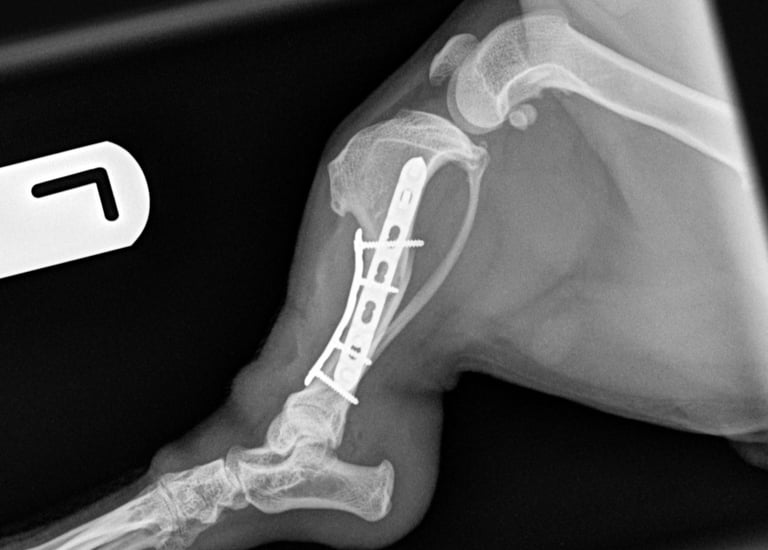

The fracture site was identified and anatomically reduced using bone-holding forceps. Internal fixation was achieved using dual plating in an orthogonal configuration, providing optimal mechanical stability.

Medial plate: A 1.5 mm 7-hole locking compression plate (LCP) was applied in bridging fashion, secured with two bicortical locking screws in both the proximal and distal fracture fragments.

Cranial plate: A 1.5 mm 5-hole LCP was also applied in bridging mode, with two locking screws in the proximal fragment (the most proximal bicortical and the distal monocortical due to proximity to the fracture line), and two bicortical locking screws in the distal fragment.

Postoperative radiographs confirmed excellent implant positioning, appropriate fracture alignment, and good apposition of fracture ends (Fig. 3 and 4).

Fig. 4